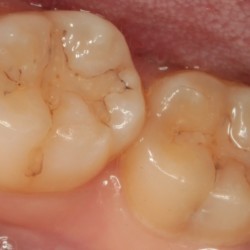

歯とつめものの隙間の虫歯

-

コンポジットレジン修復後